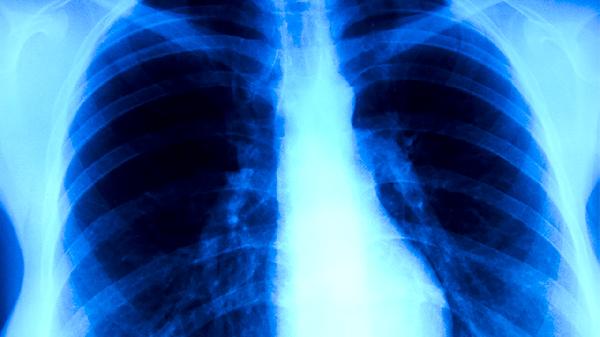

肺结核患者通常需要在医生指导下使用异烟肼片、利福平胶囊、吡嗪酰胺片、乙胺丁醇片、链霉素注射液等抗结核药物进行规范治疗才能治好。

肺结核的治疗强调早期、联合、适量、规律和全程用药,患者切不可自行选择或停用药物。在漫长的治疗过程中,除了严格遵医嘱服药,患者还需注重生活护理。饮食上应保证充足的热量和优质蛋白摄入,多吃鸡蛋、牛奶、瘦肉和豆制品,同时补充富含维生素的新鲜蔬菜水果,以增强机体修复能力。注意休息,避免劳累,居住环境应保持通风良好,阳光充足。根据身体状况进行适度的康复锻炼,如散步、太极拳等,有助于改善心肺功能。务必戒烟戒酒,定期复查胸部影像学和痰菌检查,以评估疗效。良好的心态和家庭支持对坚持完成治疗至关重要,如有任何不适或疑问,应及时与主治医生沟通。